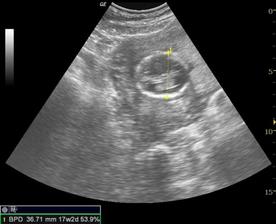

Nasa fazulka-Nellynka

Veď ja meškááám! A nie málo!!! Schytila som babytest a bežala som na WC. A hádajte! Sú tam. Dve ||. KRÁSNE, TUČNÉ A MOJE!!! Bolo to 9.9. 2oo7.